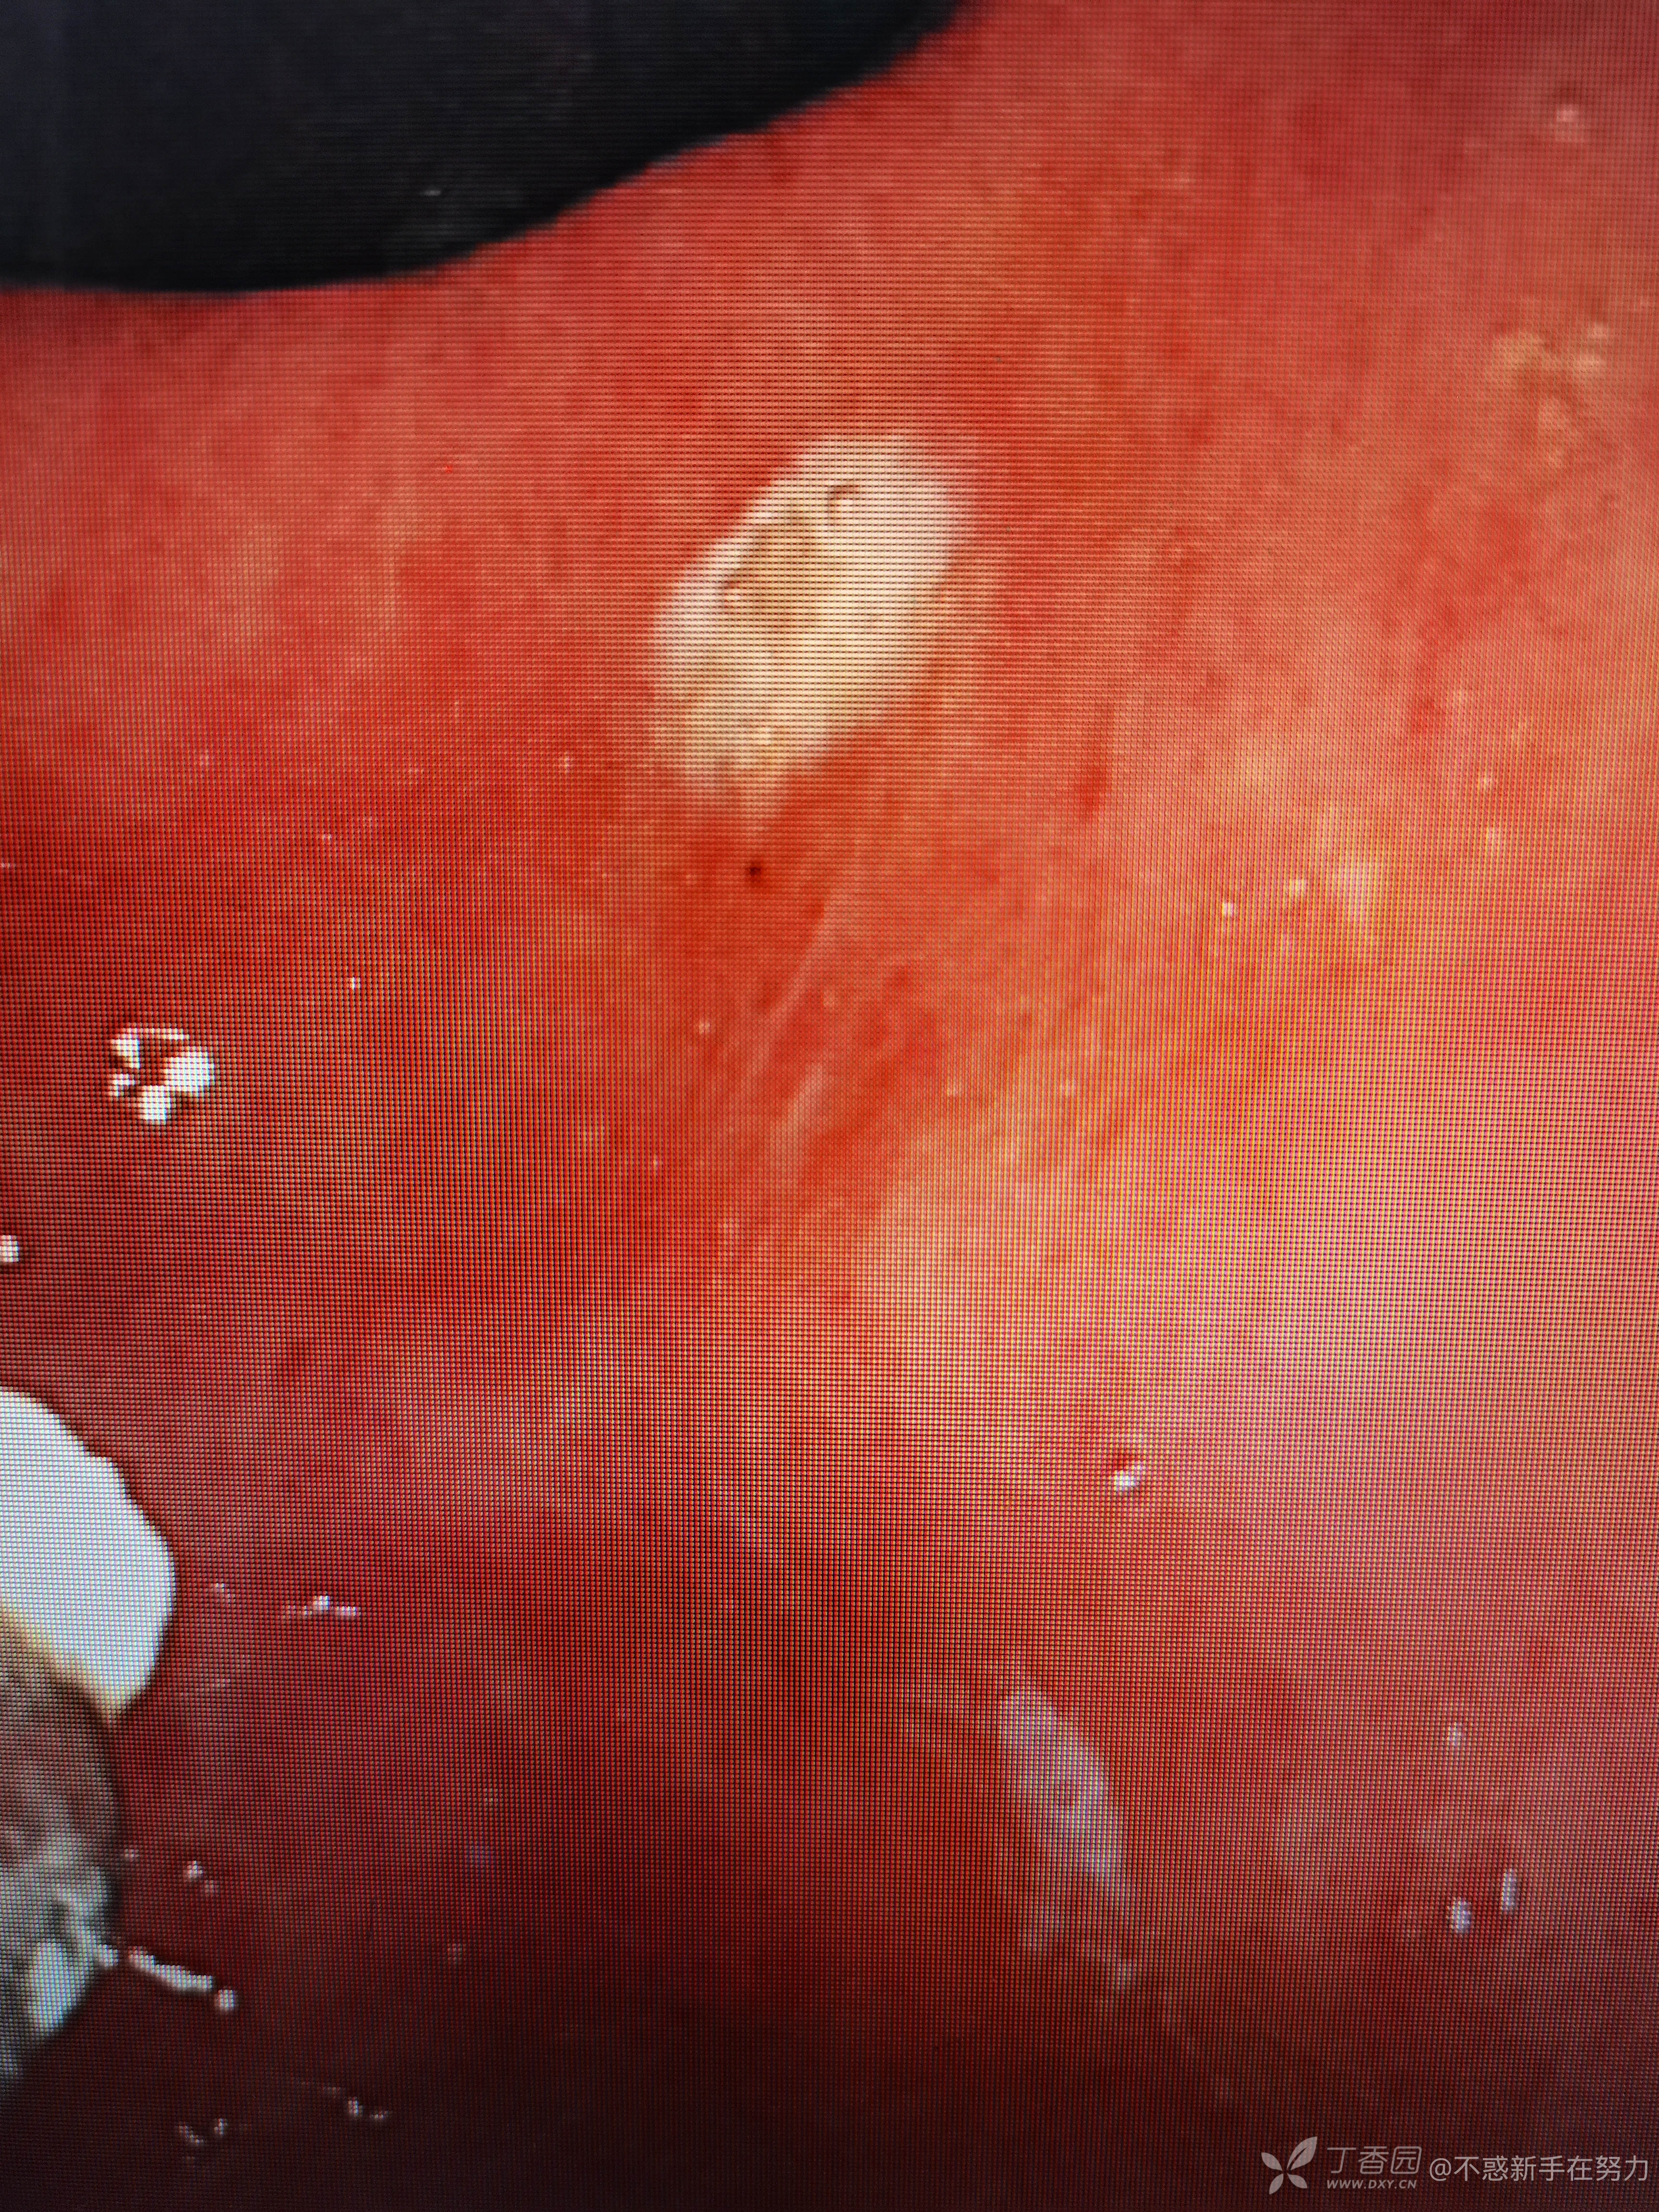

附带几张平常做的内镜下手术,都是简单的,见笑了!顺便来寻找一下自信心!毕竟这里这么多老师。